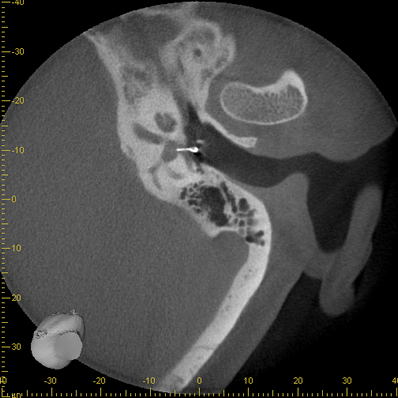

Bilder Ohr

Ambossarrosion mit Stapesprothese Stapesprothese Teflon (Causse) PORP auf Stapes PORP Titan auf Stapes PORP PORP Titan disloziiert Otosklerose Otoskleroseherd TORP Pauke nicht belüftet TORP unter Knorpelinsel disl.